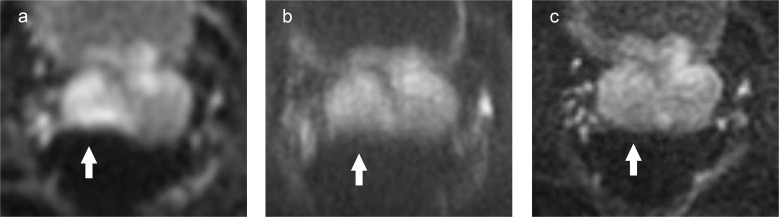

Purpose: To compare objective and subjective image quality, lesion conspicuity, and apparent diffusion coefficient (ADC) of high-resolution multiplexed sensitivity-encoding diffusion-weighted imaging (MUSE-DWI) with conventional DWI (c-DWI) and reduced FOV DWI (rFOV-DWI) in prostate MRI.

Methods: Forty-seven patients who underwent prostate MRI, including c-DWI, rFOV-DWI, and MUSE-DWI, were retrospectively evaluated. SNR and ADC of normal prostate tissue and contrast-to-noise ratio (CNR) and ADC of prostate cancer (PCa) were measured and compared between the three sequences. Image quality and lesion conspicuity were independently graded by two radiologists using a 5-point scale and compared between the three sequences.

Results: The SNR of normal prostate tissue was significantly higher with rFOV-DWI than with the other two DWI techniques (P ≤ 0.01). The CNR of the PCa was significantly higher with rFOV-DWI than with MUSE-DWI (P < 0.05). The ADC of normal prostate tissue measured by rFOV-DWI was lower than that measured by MUSE-DWI and c-DWI (P < 0.01), while there was no difference in the ADC of cancers. In the qualitative analysis, MUSE-DWI showed significantly higher scores than rFOV-DWI and c-DWI for visibility of anatomy and overall image quality in both readers, and significantly higher scores for distortion in one of the two readers (P < 0.001). There was no difference in lesion conspicuity between the three sequences.

Conclusion: High-resolution MUSE-DWI showed higher image quality and reduced distortion compared to c-DWI, while maintaining a wide FOV and similar ADC quantification, although no difference in lesion conspicuity was observed.